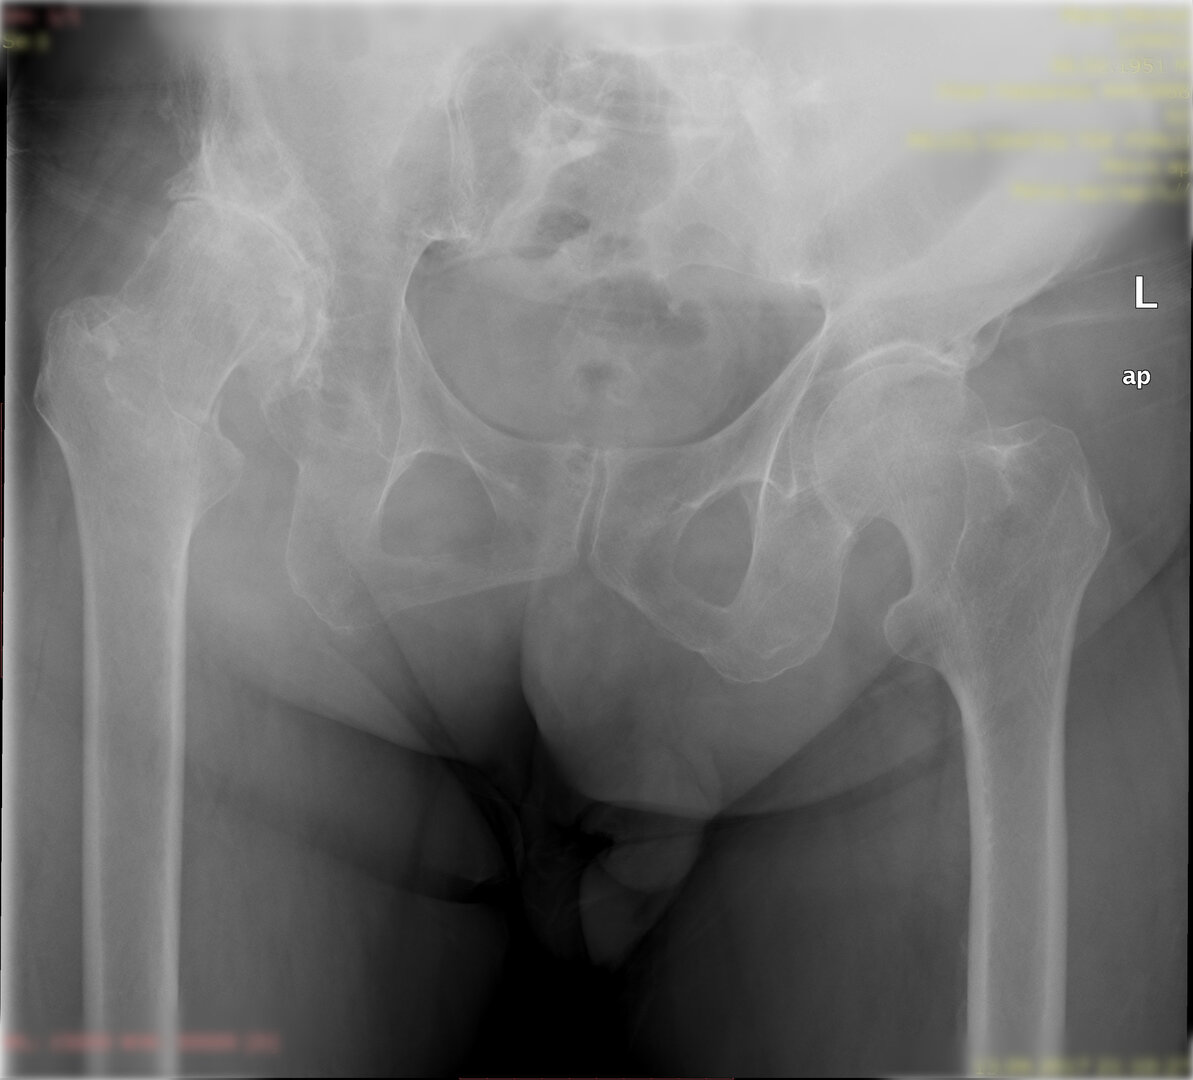

Peki kalça protezi ameliyatın da neler yapıyoruz? Diz protezi ameliyatındaki benzer aşamaları uyguluyoruz. Kalça eklemi dize göre yapısal olarak ve çalışma sistemi olarak farklıdır. Kalça eklemi bir yuva ve onun içinde hareket eden femur başı dediğimiz bir toptan oluşur. Kalça eklemi kireçlenmesinde bu baş ve yuva yüzeyindeki kıkırdakların aşınması sonucu başın yuvarlaklığı kaybolur, sonuçta ağrı ve hareket kısıtlılığı ortaya çıkar. Bu yüzeyleri değiştirirken öncelikle bu başı kesip atıyoruz. Daha sonra yuvayı yine kılavuzlarla oyup uygun büyüklükteki protezi sıkıştırdıktan sonra en az 2 vida ile kemiğe adapte ediyoruz. Daha sonra alt uyluk kemiğini yine kılavuzlar yardımı ile oyduktan sonra kemiğe adapte ediyoruz ve sistemi birleştiriyoruz.

Büyütmek için üzerine tıklayınız.